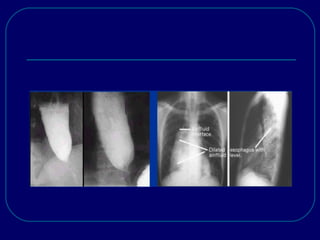

ACHALASIA:

 CXR show a widened mediastinum, air-fluid level& absent

gastric air bubble.

 Barium swallow shows a dilated esophagus, air-fluid level,

delayed esophageal emptying& a smooth, tapered “bird’s

beak” deformity at the LES.

ACHALASIA:  CXR showa widened mediastinum, air-fluid level& absent gastric air bubble.  Barium swallow shows a dilated esophagus, air-fluid level, delayed esophageal emptying& a smooth, tapered “bird’s beak” deformity at the LES.  Manometry show characteristic incomplete relaxation of the LES with swallows& complete aperistalsis in the body.  LES pressure may or may not be elevated.  Neither radiographic nor manometric criteria can effectively exclude achalasia secondary to cancer, so endoscopy must be performed prior to treatment.